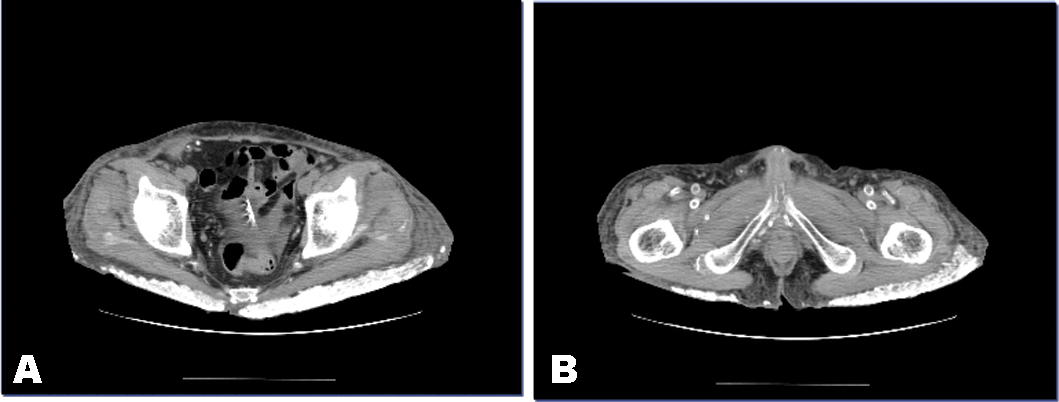

He underwent hemodialysis on admission to our hospita. His condition improved gradually. However, he had lumbago and had stiffness of the hip. His abdominal computed tomography (CT) scan is shown in Figure 1. Remarkable metastatic calcification was noted around his hips. His laboratory results were as follow: Hb - 7.1 g/dL, serum total protein - 5.2 g/dL, serum albumin - 2.0 g/dL, BUN - 49 mg/dL, Cr - 6.3 mg/dL, Na - 134 mEq/L, K - 4.3 mEq/L, Cl - 103 mEq/L, Ca - 10.2 mg/dL, P - 6.2 mg/dL, ALP - 488 U/L, serum ß2-microgloburin - 35.9 µg/mL, CRP - 3.8 mg/dL, intact-PTH - 6 pg/mL. Because serum calcium levels were very elevated, the administration of vitamin D3 [1a, 3a-(5Z, 7E)-isomer 1-hydroxycholecalciferol] was discontinued

Figure 1: Severe metastatic calcification around A) hip, and B) vascular wall, in the patient with transplanted kidney failure.